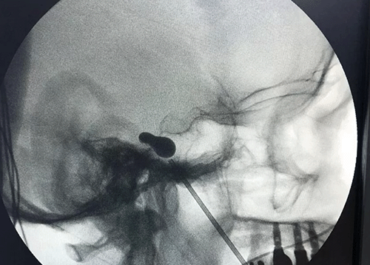

Compressão do Nervo Trigêmeo para Neuralgia Trigeminal

A dor do nervo trigêmeo é considerada por muitos como a pior dor que uma pessoa pode sentir. Ela é tão forte que algumas pessoas, tão desesperadas que ficam, sentem vontade de interromper a própria vida. Quando a dor está esparramada na face, uma das alternativas é realizar uma compressão do gânglio de Gasser com […]